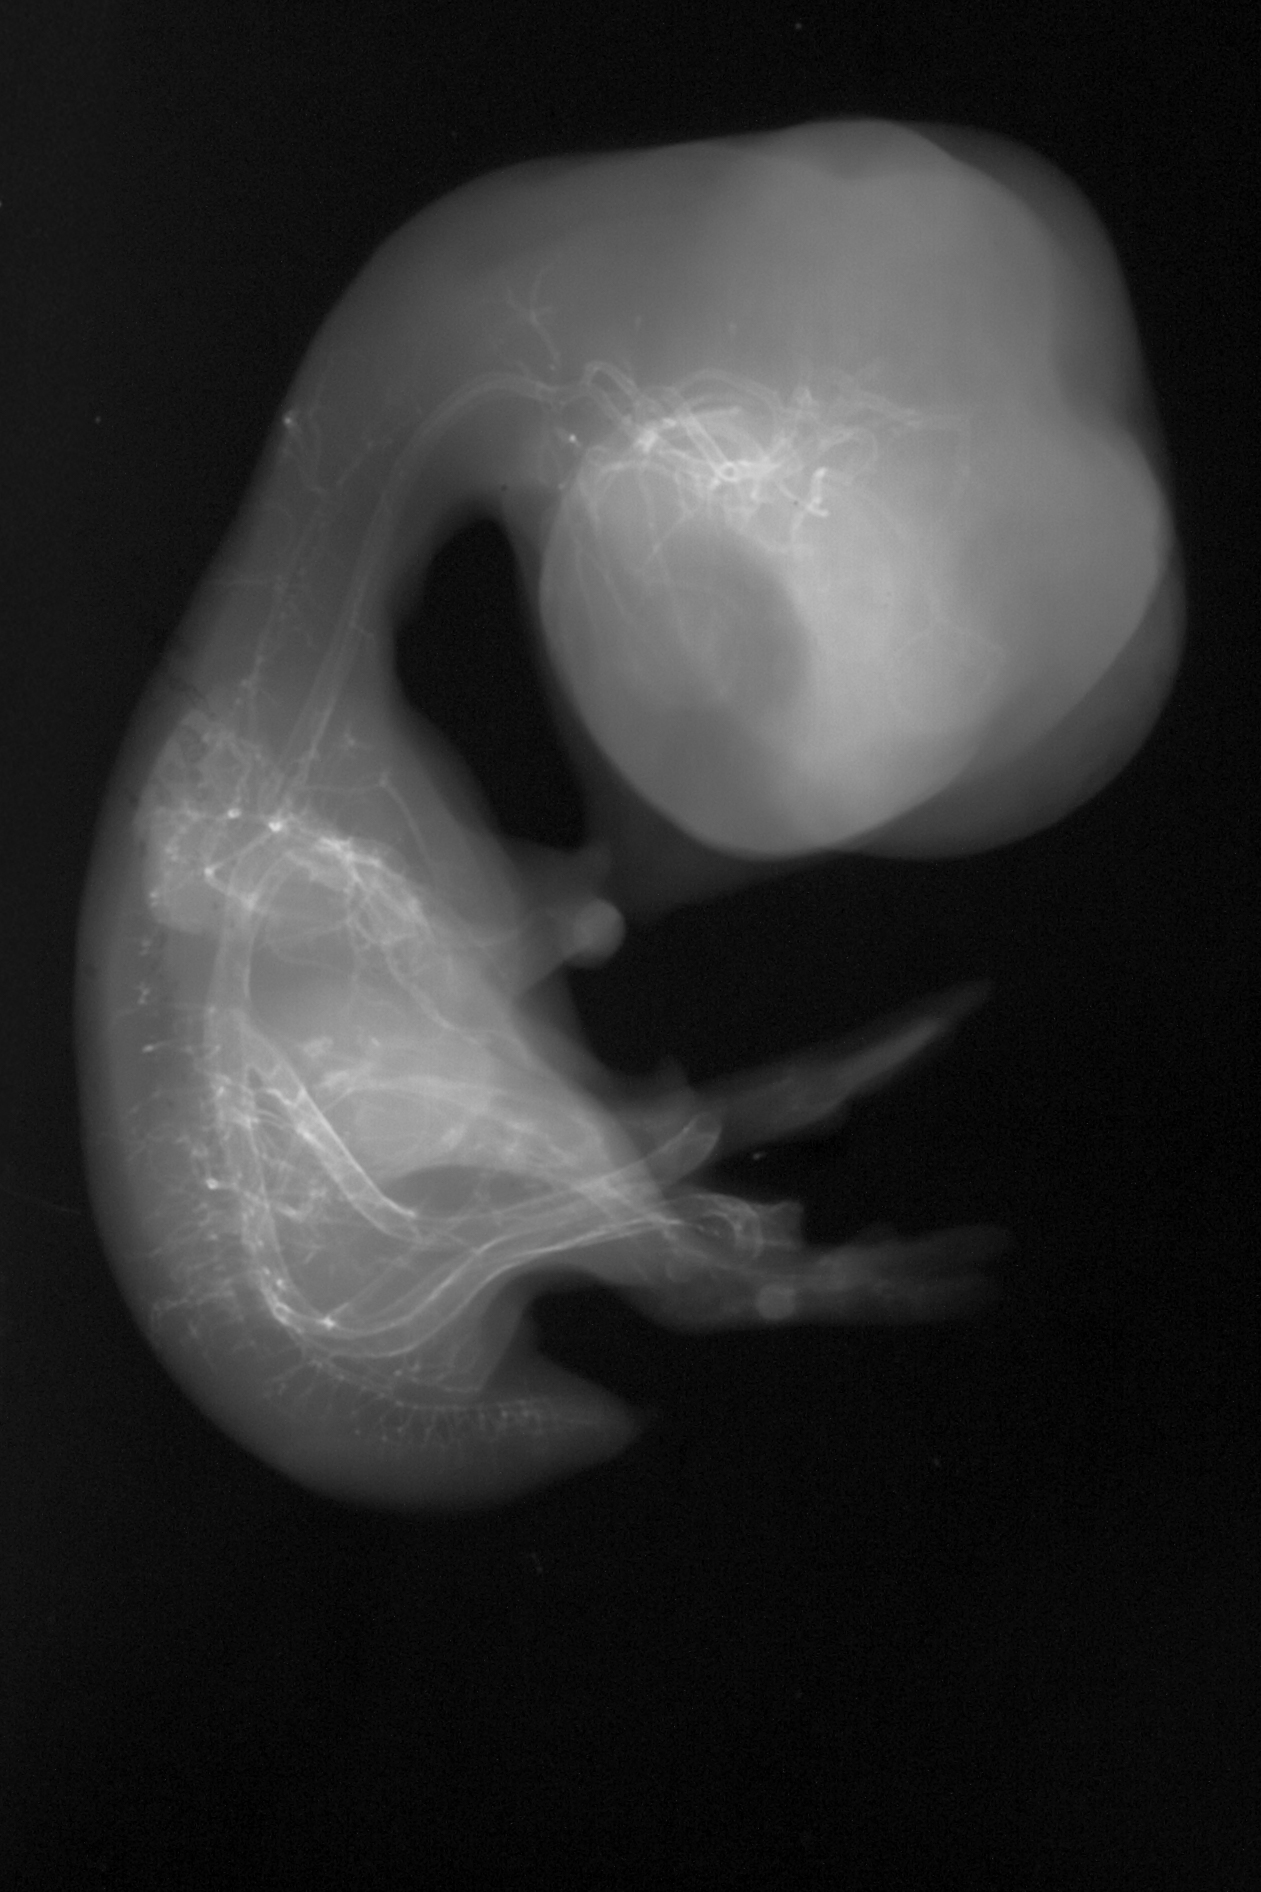

Chick Embryo Microangiography

Hamburger-Hamilton (HH) Stage 35 (approx. 8.5 - 9 days)

Drawing